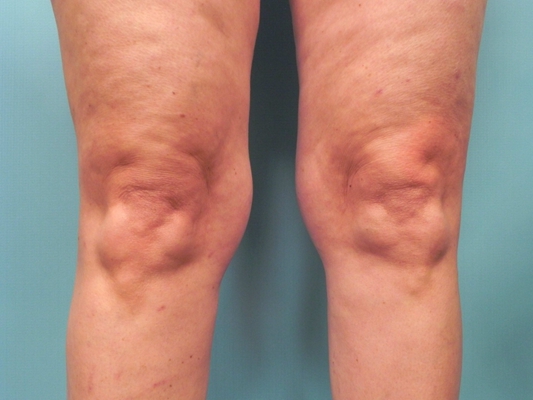

骨質增生圖片

膝蓋骨質增生 (50)